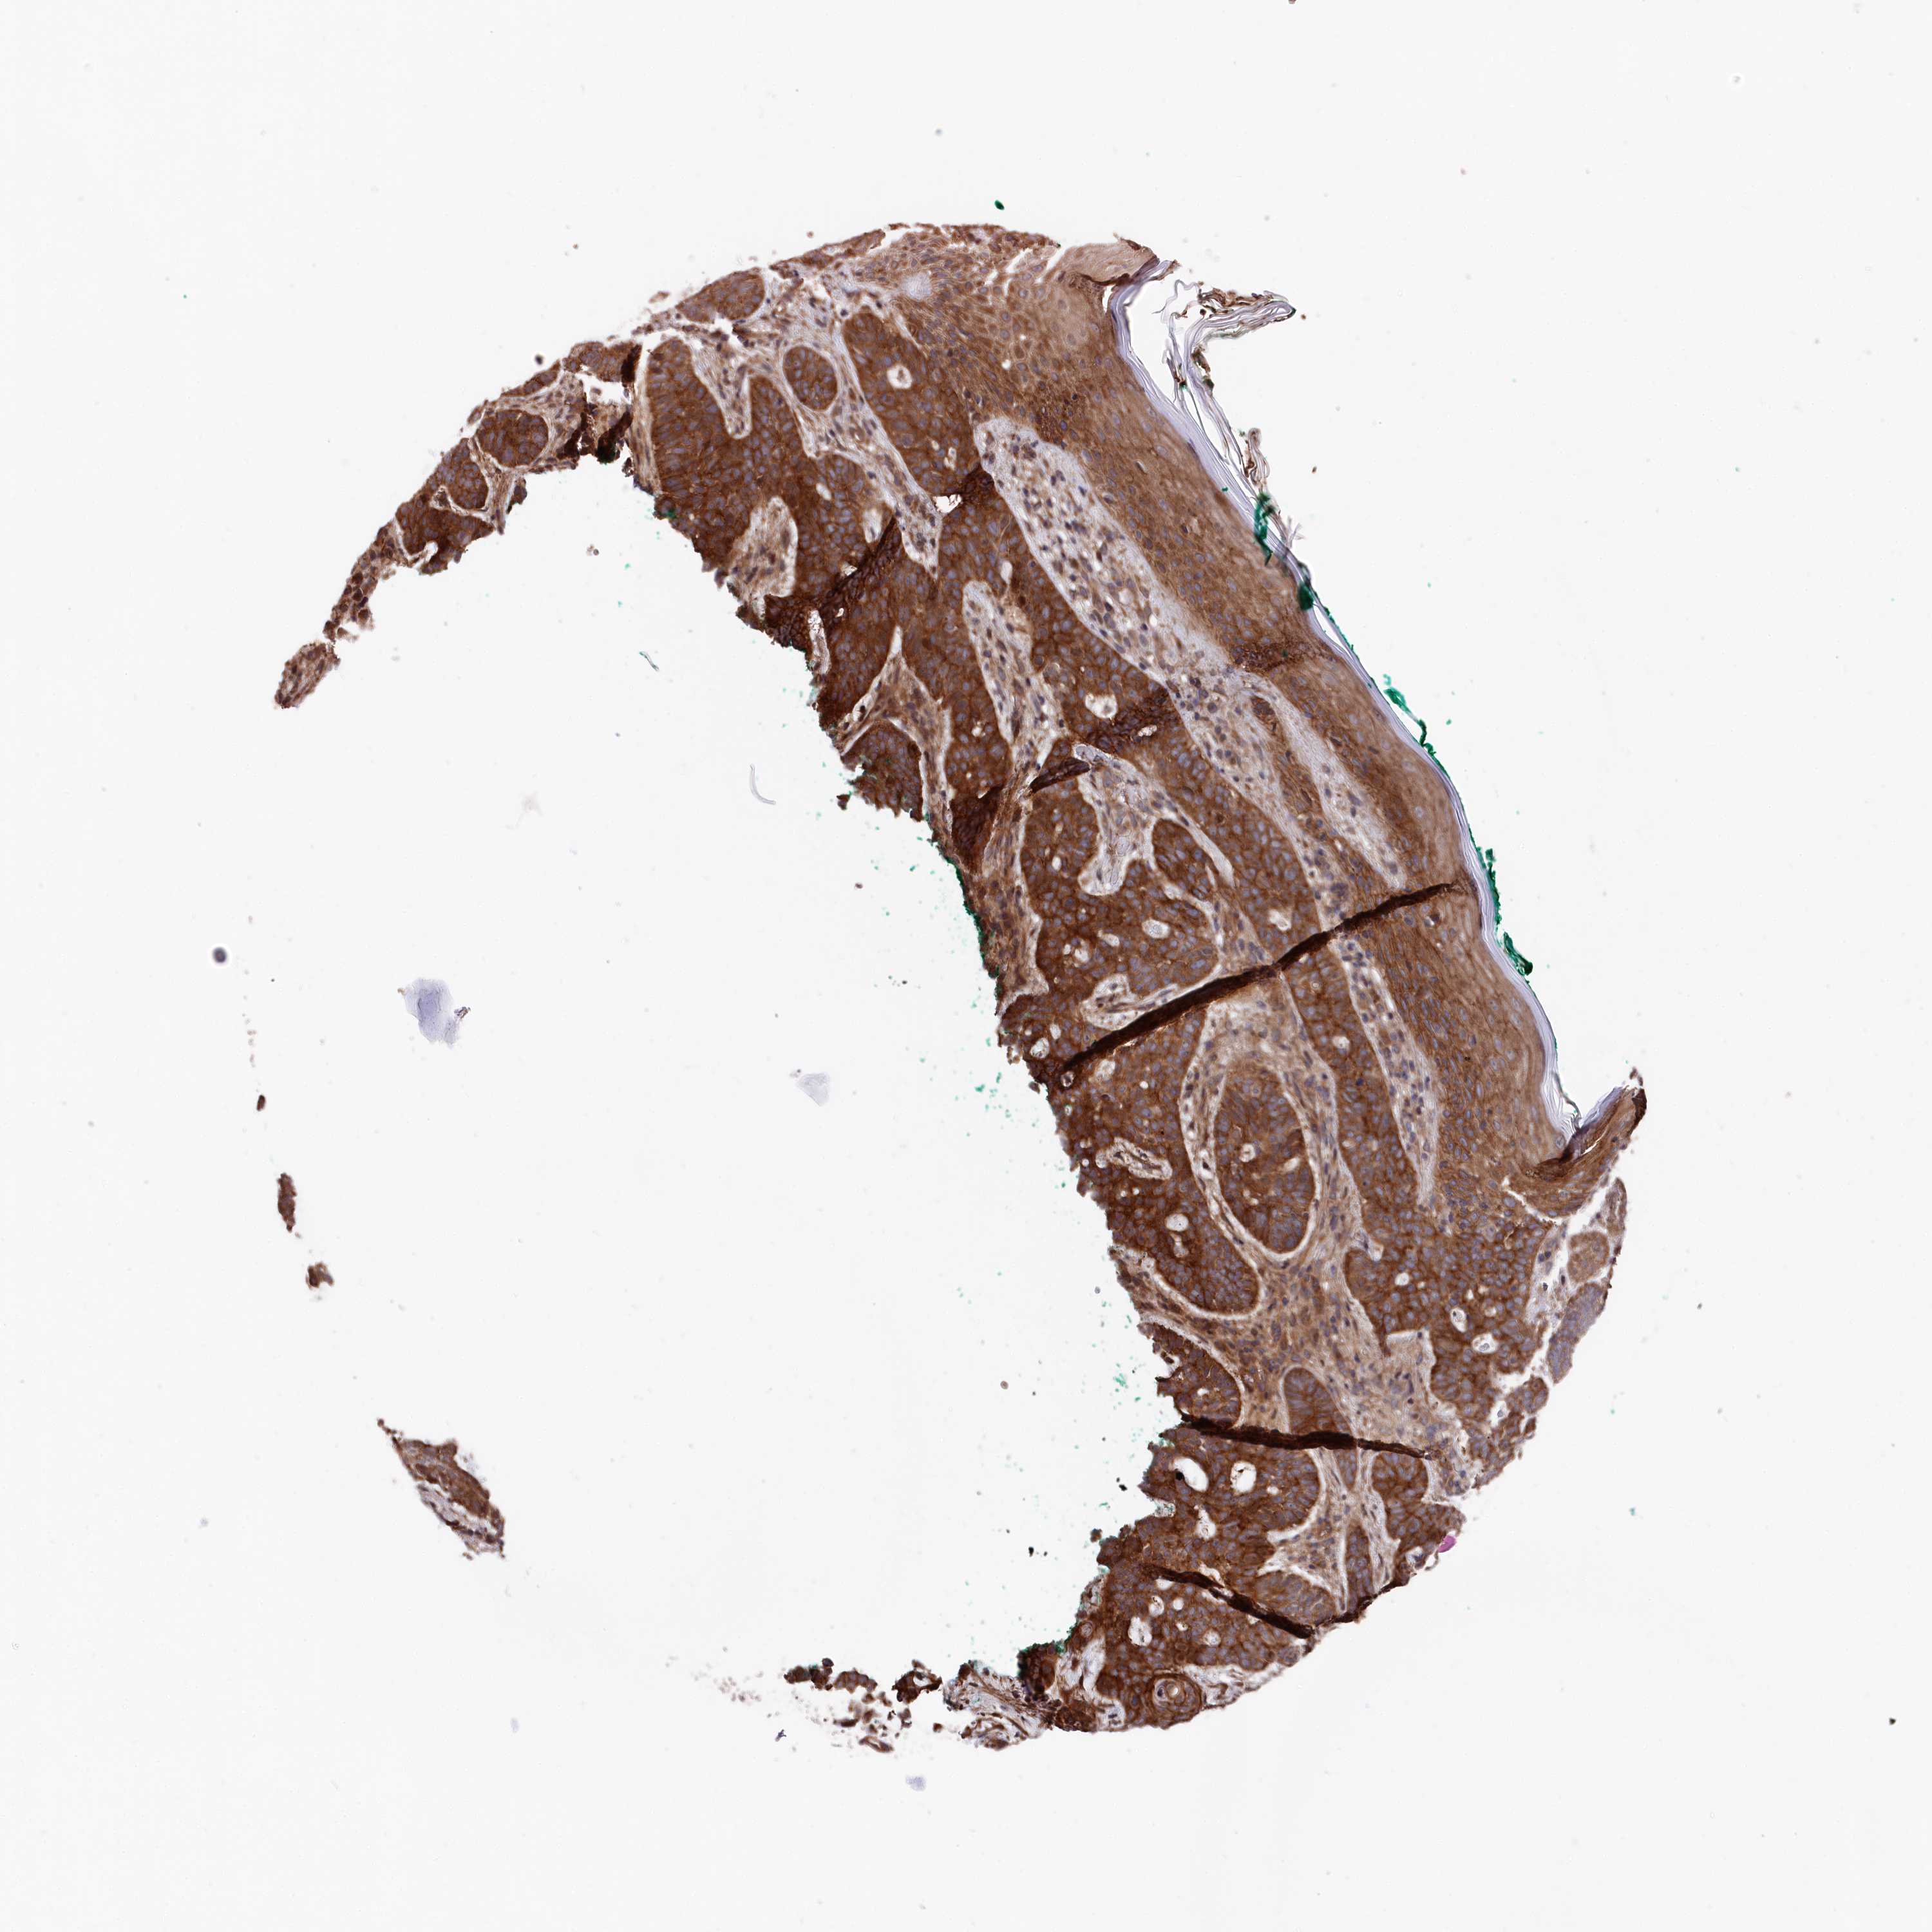

CANCER SKIN CANCER Show tissue menu

Basal cell and squamous cell cancer

SKIN CANCER - Protein expressioni

A mouse-over function shows sample information and annotation data. Click on an image to view it in a full screen mode. Samples can be filtered based on level of antibody staining by selecting one or several of the following categories: high, medium, low and not detected. The assay and annotation is described here.

Each image is clickable and will lead to virtual microscopy that enables deeper exploration of all samples and also displays staining intensity scores, fraction scores and subcellular localization as well as patient and tissue information for each sample.

Antibody HPA037929

Antibody HPA037930

Staining

High

Medium

Low

Not detected

Intensity

Strong

Moderate

Weak

Negative

Quantity

>75%

75%-25%

<25%

None

Location

Nuclear

Cytoplasmic/membranous

Cytoplasmic/membranous,nuclear

Basal cell carcinoma

Squamous cell carcinoma, NOS

Squamous cell carcinoma, metastatic, NOS